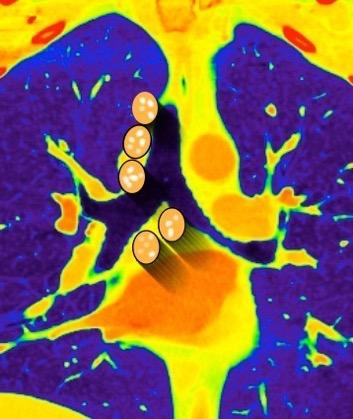

136. PERLAS NEGRAS, SIGNO DE LAS

Ramana. RV et al. The “Cluster of black pearls” sign of sarcoid lymphadenopathy: a new sign on thin-section contrast-enhanced multidetector CT. Clinical Radiology 2017

2-3 cm por debajo del espacio subcarinal

Linfoma de Hodgkin escleroso-nodular

Mediastinitis fibrosa. Fibrosis retroperitoneal.

10-20% de los casos de FM difusa

Reacción a Enf. Autoinmunes. (LED, AR)

Hematopoyesis extramedular

Metersigida / Radioterapia. Enf. inmunoglobulina IgG4. (Riedel, Colangitis, etc.)